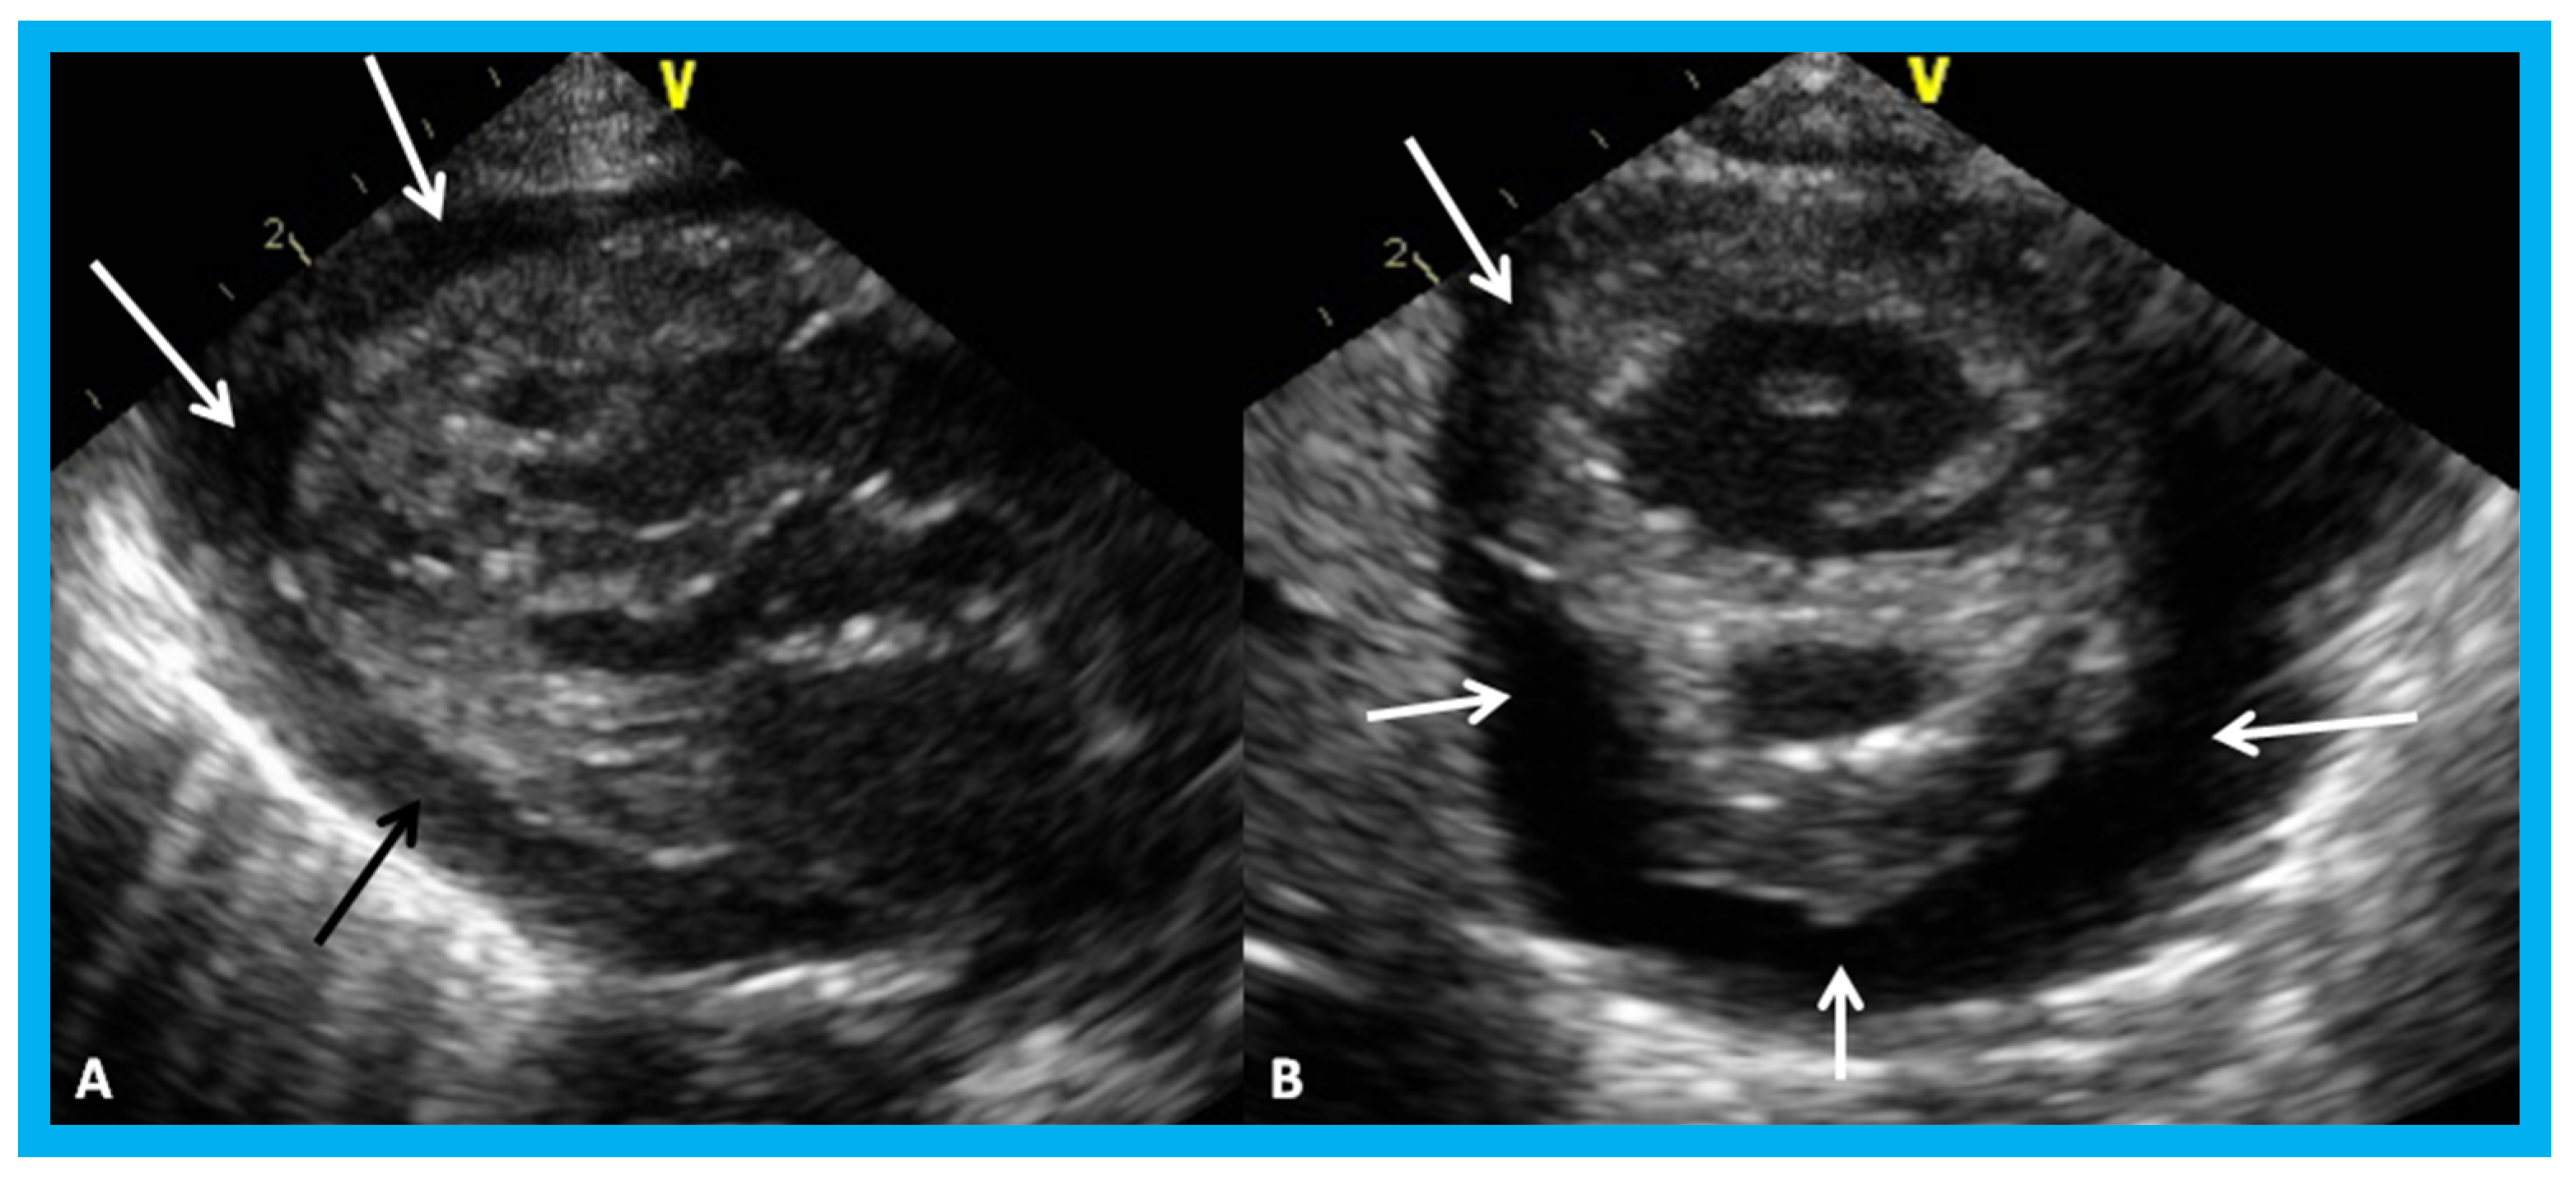

Figure 30. Apical four-chamber (A,B) and parasternal short axis (C) views of the heart in an infant with cardiomegaly showing a significant pericardial effusion (thick arrows): Fibrin strands in the effusion are shown (thin arrows).

Figure 31. Parasternal long (A) and short (B) axis views of the heart in a baby with cardiomegaly demonstrating a large pericardial effusion (arrows).